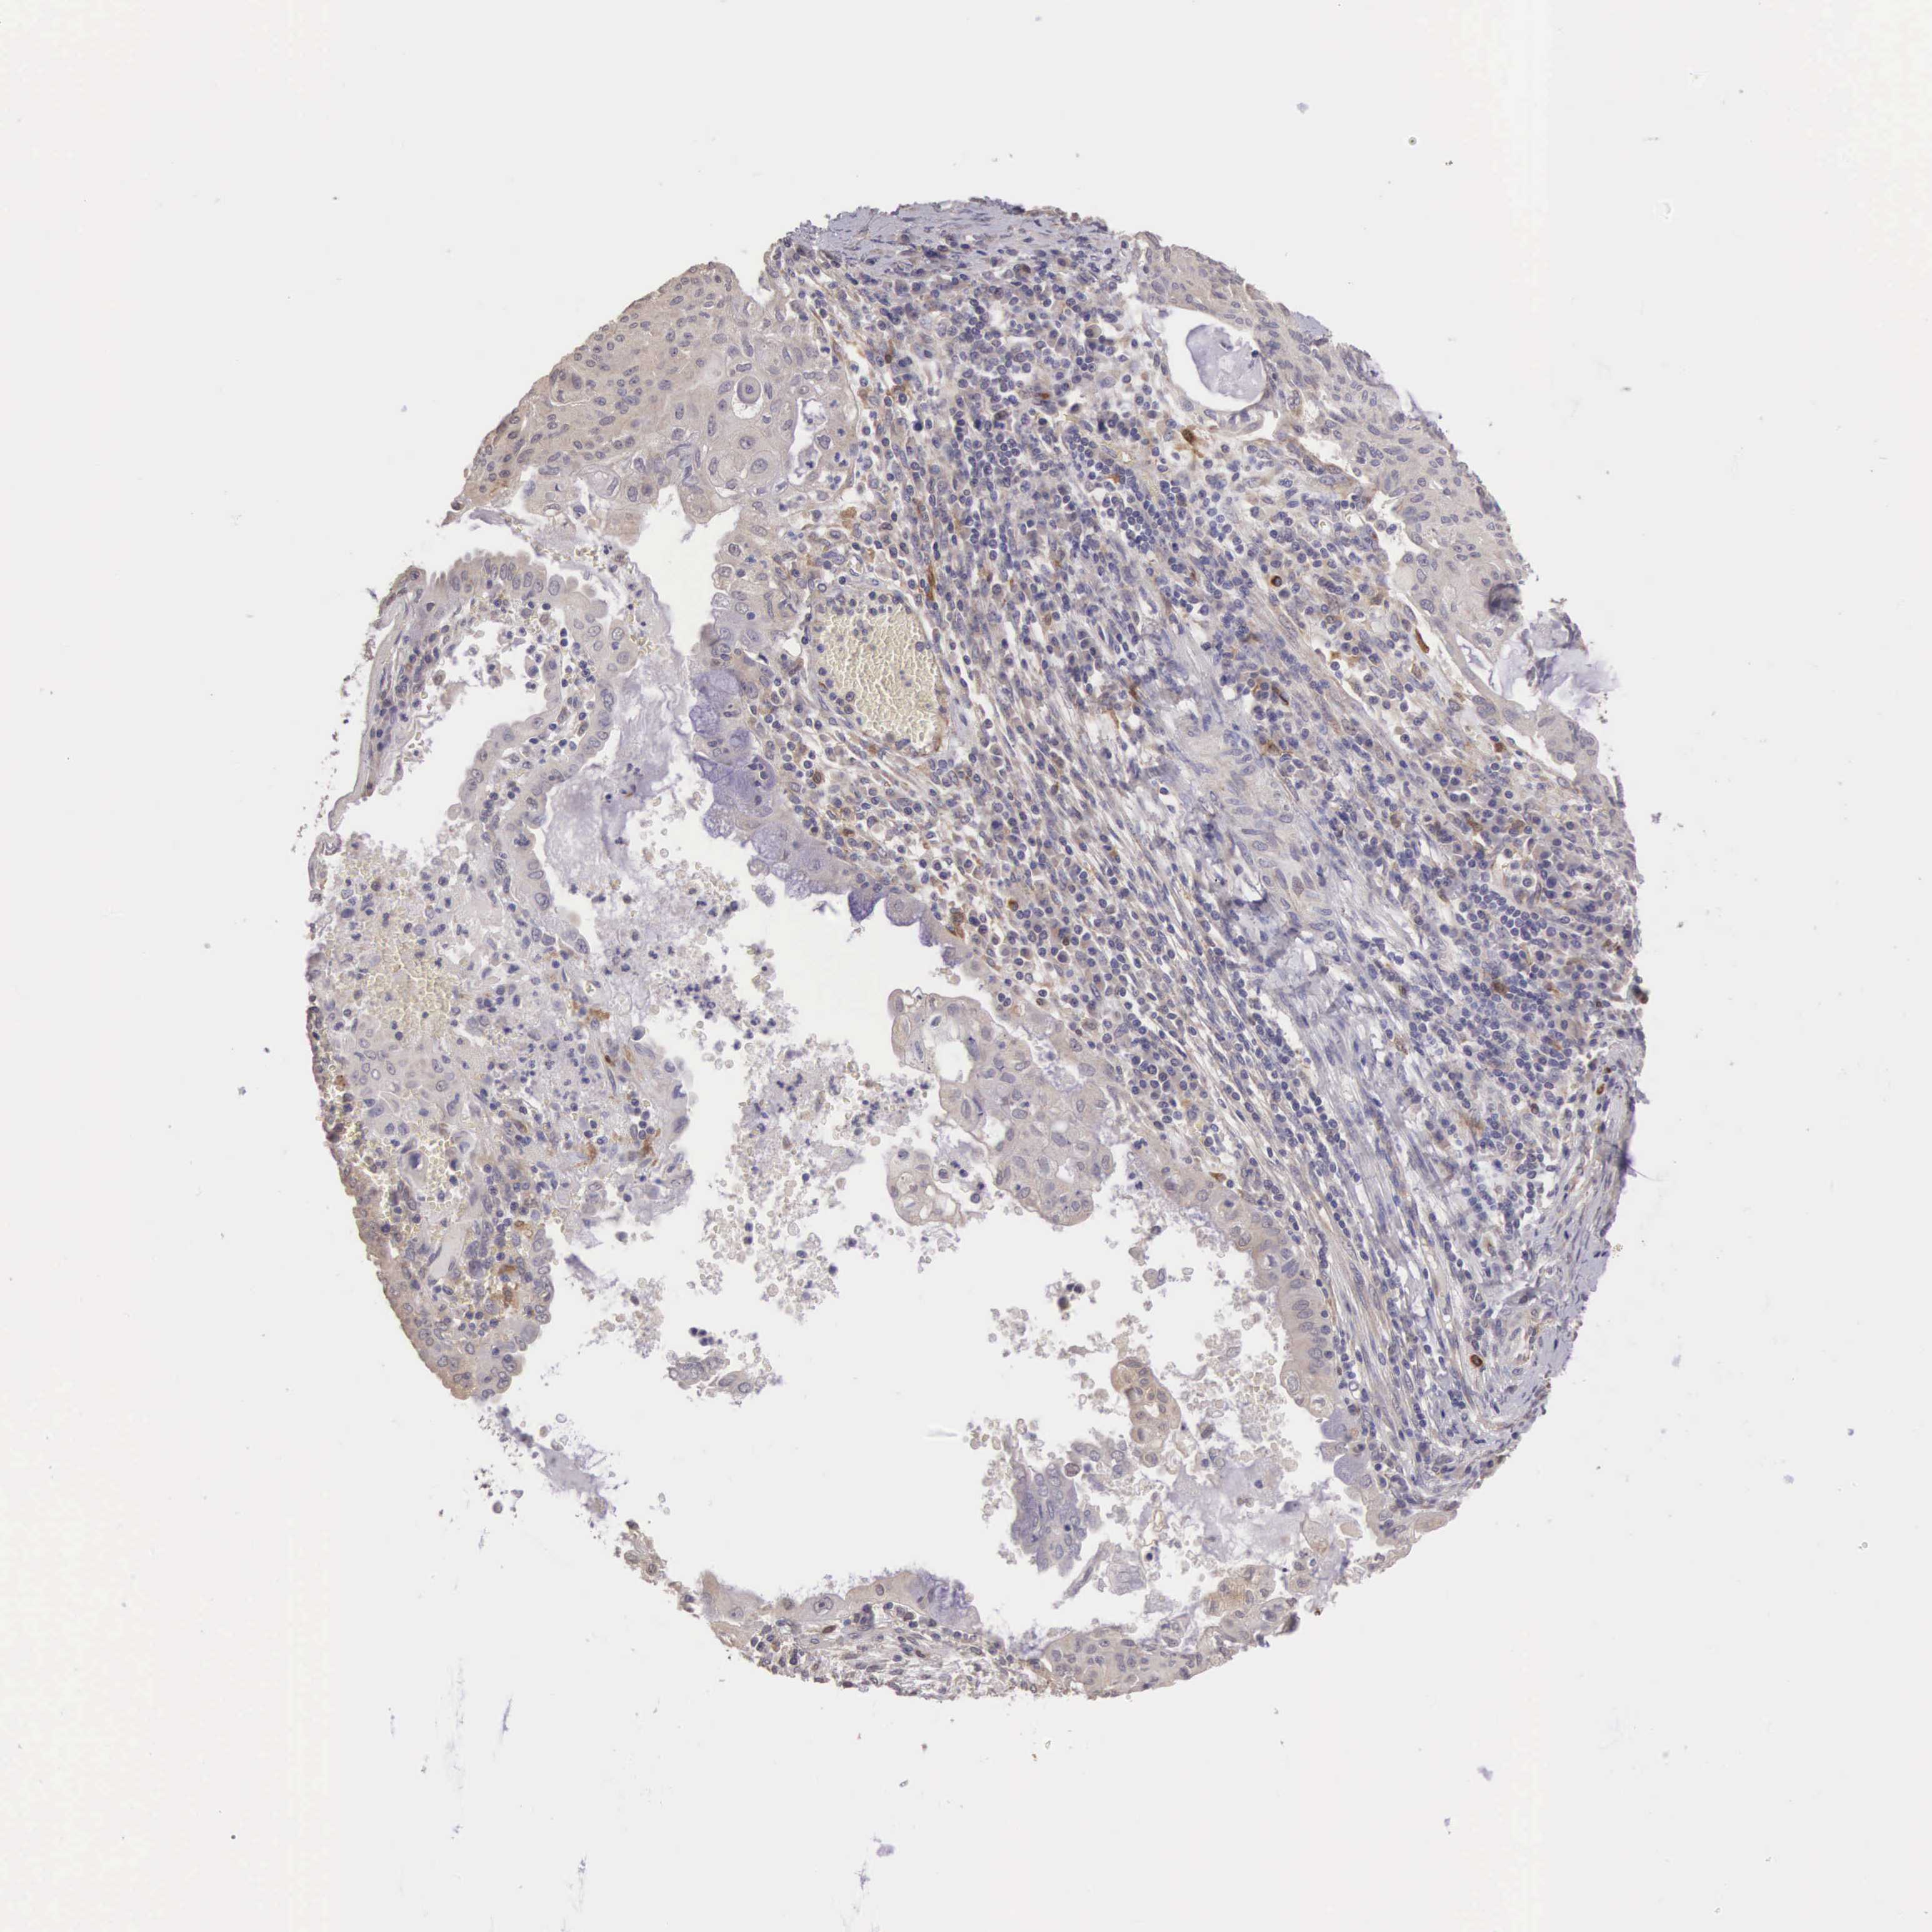

CDC45